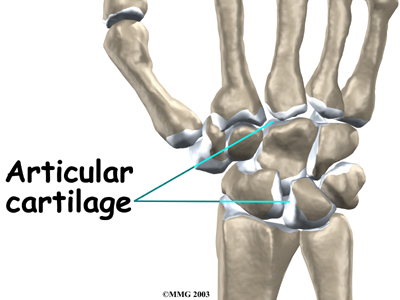

is the material that covers the ends of the bones of any joint. Articular cartilage can be up to one-quarter of an inch thick in the large, weight-bearing joints. It is thinner in joints such as the wrist that don't support a lot of weight. Articular cartilage is white, shiny, and has a rubbery consistency. It is slippery, which allows the joint surfaces to slide against one another without causing any damage.

The function of articular cartilage is to absorb shock and provide an extremely smooth surface to make motion easier. We have articular cartilage essentially everywhere that two bony surfaces move against one another, or articulate. In the wrist, articular cartilage covers the sides of all the carpals and the ends of the bones that connect from the forearm to the fingers.

Articular cartilage

Articular cartilage